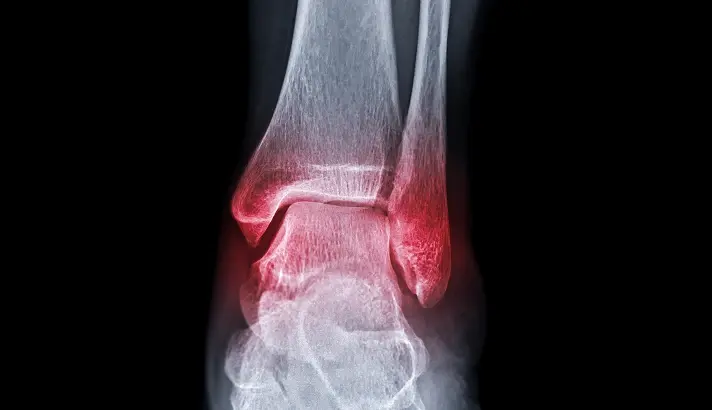

X-ray Imaging

X-rays are the primary imaging tool used to confirm an ankle fracture. Images are typically taken from several angles to identify the location of the break and assess whether the bones remain properly aligned. The X-ray also helps determine whether the ankle joint is stable or if there are signs of widening that suggest associated ligament injury.

Stress or Weight-Bearing X-rays

If the initial X-rays show a fracture but stability is uncertain, additional views may be taken. In selected cases, stress views or weight-bearing X-rays are performed to assess whether the bones shift abnormally under load, which would indicate instability and influence treatment decisions.